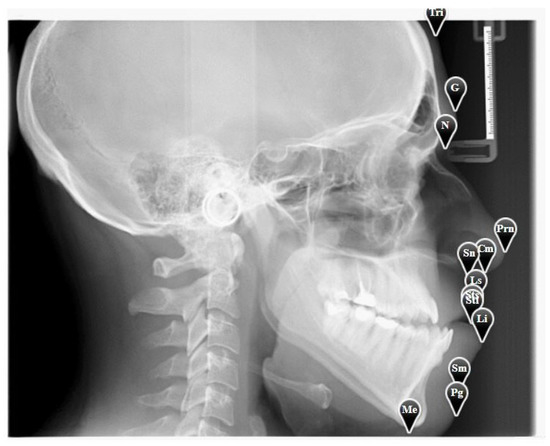

In this study, we use 13 landmarks from the soft tissue area as shown in Table 1.

The user should click “Annotations” to start annotating the above landmarks, or if he has already done so, he can update those annotations easily. For illustration purposes, we show a sample X-ray image with the expert annotations in Figure 4.

Figure 4. A sample X-ray image with annotation.